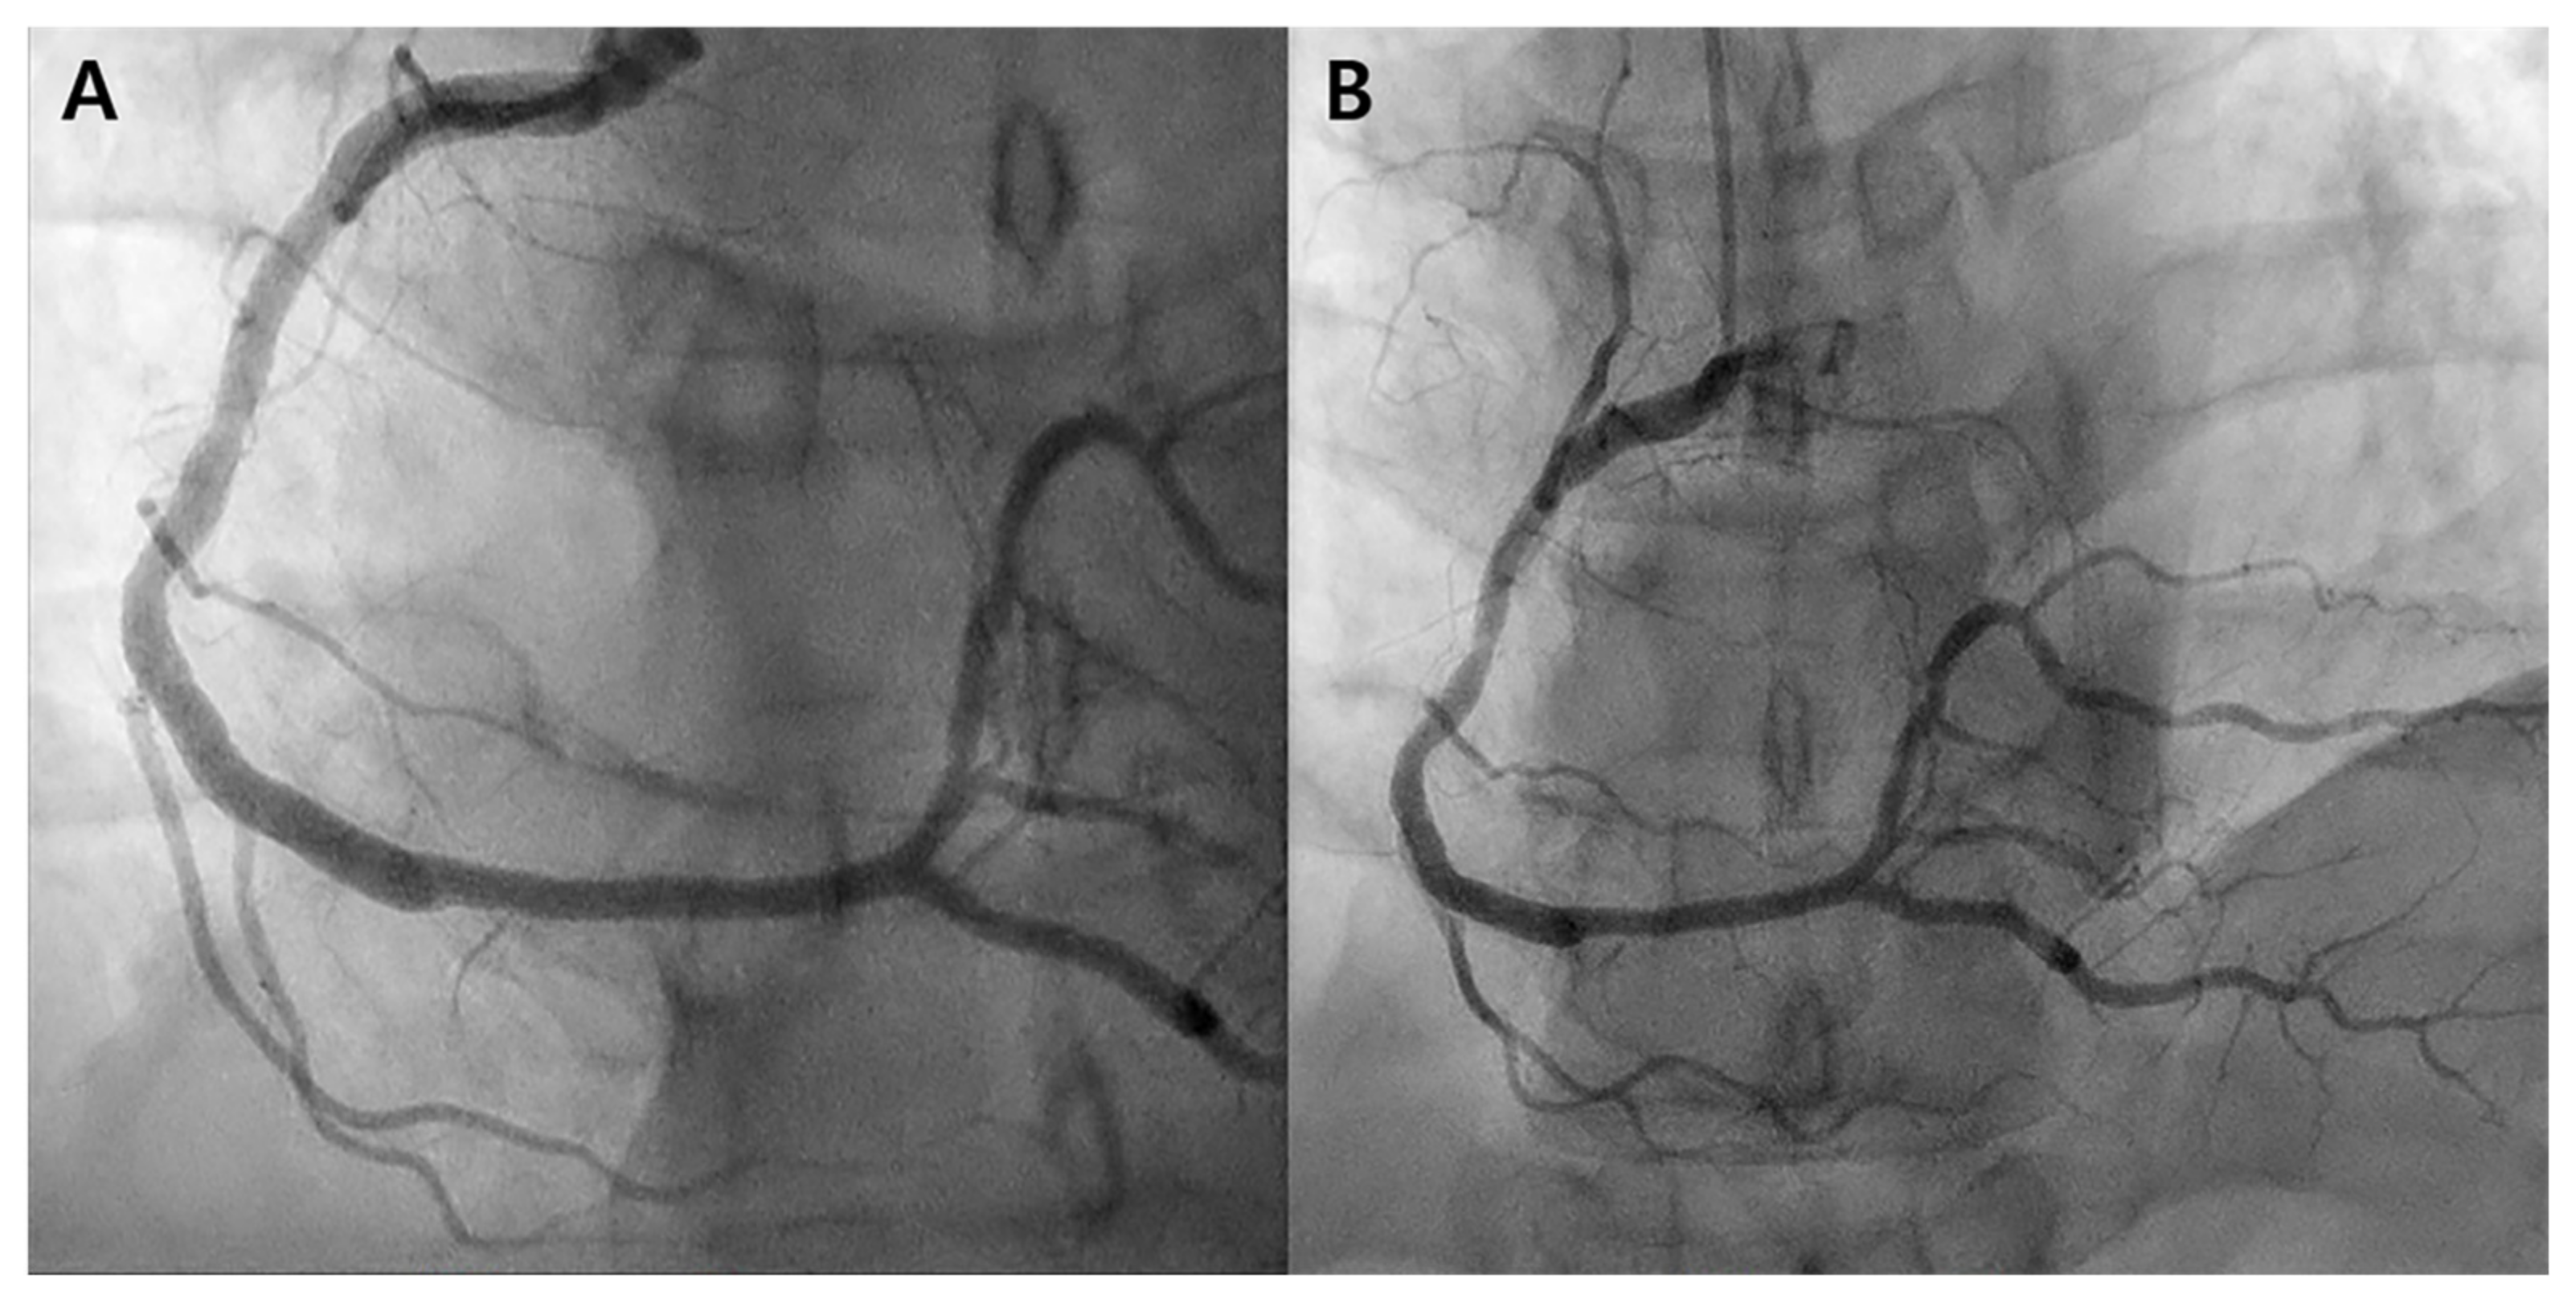

One year later, the patient presented again with complaints of chest pain and shortness of breath during exercise. Subsequent coronary angiography revealed a newly developed subtotal occlusion causing TIMI grade 1 flow in the proximal RCA area (Figure 2A). Optical coherence tomography (OCT) was then performed to identify the lesion features, revealing a de novo lesion accompanied by plaque rupture (Figure 2B). A new stent was promptly inserted at the lesion site (Figure 2C).

Figure 2. Second coronary angiography. (A) Right coronary angiography before intervention. Subtotal occlusion has newly developed in the proximal right coronary artery (RCA), outside the proximal part of the previous stent. (B) Optical coherence tomography. Plaque rupture is observed in the de novo lesions of the proximal RCA. (C) Right coronary angiography post-intervention. The flow recovered after stent insertion into the proximal RCA.